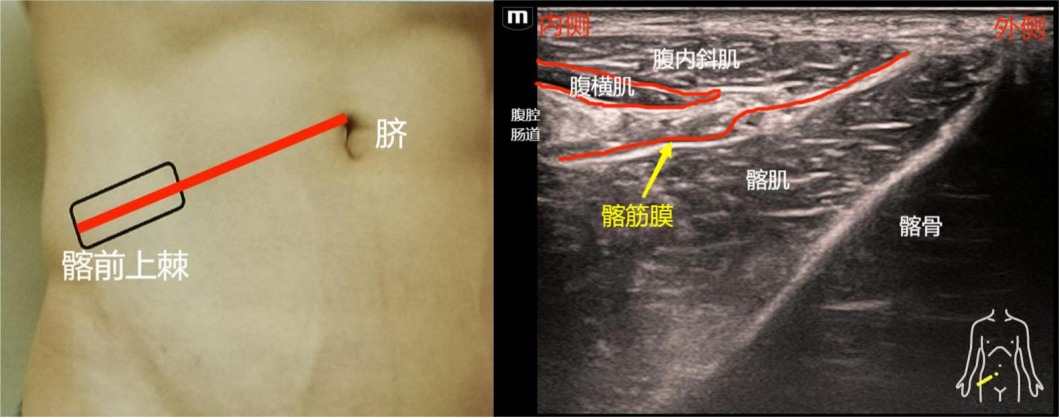

(二)山坡征法:也为药物注射在腹股沟韧带上的髂筋膜间隙阻滞。探头放置在髂前上棘和脐部连线外1/3处,探头在人体尾侧方,髂骨声像为斜向下的高回声影,形成像山坡样的图形。

扫查方法:扫查关键点也是先找髂肌,然后顺髂肌找其它的结构。探头先放置在髂前上棘的内侧,与髂前上棘和脐连线外1/3处相平行或重合。想要快速获取山坡征样的图像,扫查手法的关键点是:探头柄端向腹侧倾斜,使探头声束方向尽量正对髂骨面。也就是以探头内侧端为支点,使内侧端(靠近脐侧)往下压,同时探头的外侧端(髂前上棘处)顺势往上翘起,但不能悬空,保持和皮肤接触,即可容易地获得山坡样的髂骨面声像。此时髂骨的表面就是髂肌,髂肌与腹横肌筋膜、腹内斜肌筋膜之间,可认为是髂筋膜间隙。因为髂筋膜薄,超声显像难以分辨出单独的髂筋膜结构。

穿刺方法:平面内法,一般从髂前上棘侧进针(即人体外侧向腹内侧进针),因为外侧向内侧进针,此时的进针路径可以与髂筋膜平行。如果从内侧向外侧进针,可能会增加穿刺针穿入腹腔的风险。但采用外侧向内侧进针时,由于髂前上棘非常表浅,阻碍进针路线,探头可以向内侧前方移动,避开髂前上棘,以方便进针。注射药物时,需观察药液是否在髂肌与髂筋膜之间形成液性暗区。也可平面外法,从探头长轴面的两侧进针,药液注射在髂筋膜间隙中,也需要观察药液是否在髂筋膜间隙内扩散,是否形成也行暗区。